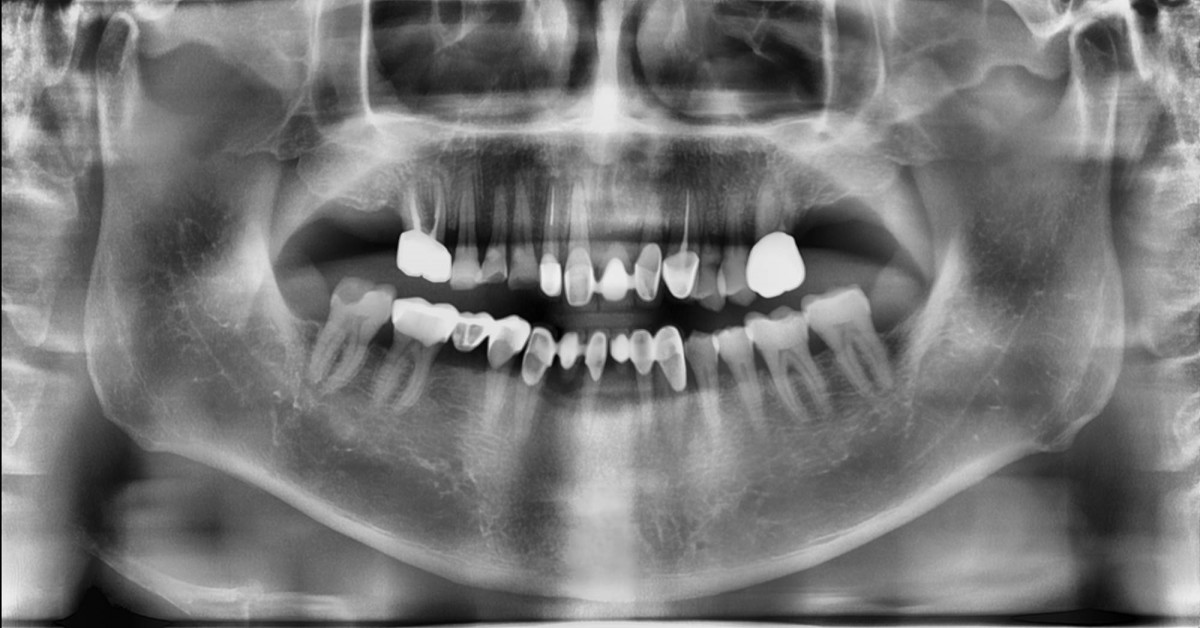

Socket Lift and Implant Placement in the right maxilla.

<GCacg> A 56-year-old male patient complained of pain in the right upper and lower jaws. And he wanted the upper first molar to be pulled out first.